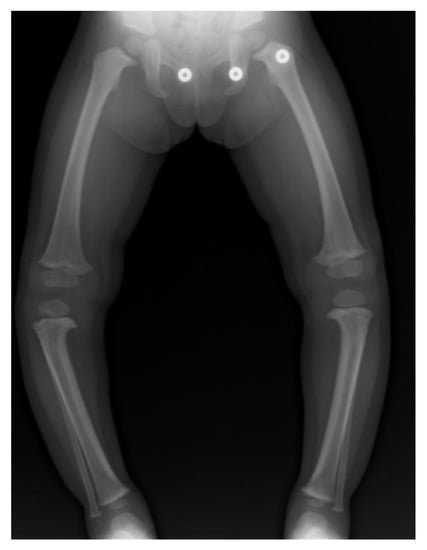

3. ITV Differential Diagnosis and Clinical Features

4. Radiographic Imaging

5. Radiographic Analysis

10. Surgical Planning